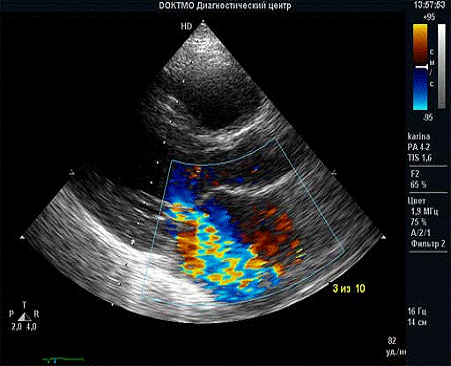

Рис.4. Фрагмент эхокардиографического исследования пациента с выраженной недостаточностью митрального клапана на фоне ревматизма.

В режиме цветного допплеровского картирования определяется значительный по объему возврат крови в левое предсердие в результате неполного смыкания пораженных митральных створок.